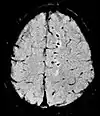

Diffusion weighted (DWI)ConventionalDWIMeasure of Brownian motion of water molecules.[26] High signal within minutes of cerebral infarction (pictured).[27]

Apparent diffusion coefficientADCReduced T2 weighting by taking multiple conventional DWI images with different DWI weighting, and the change corresponds to diffusion.[28] Low signal minutes after cerebral infarction (pictured).[29]